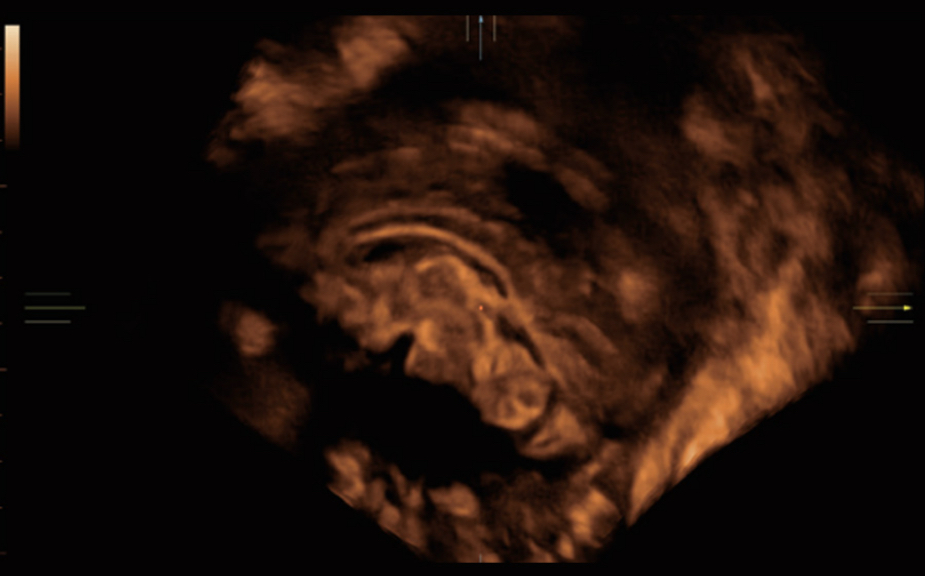

The Nuewa I9, dedicatedly designed for women and neonatal healthcare, providing an innovative experience from inside out.?These innovations are developed based on in-depth insights into complex clinical scenarios, providing accurate and timely answers as well as outstanding efficiency and remarkable user experience.

The ZST+ platform is an extraordinary innovation, representing an ultrasound evolution. Transforming ultrasound metrics from conventional beam-forming to channel data based processing. It overcomes the traditional trade-off limitation among spatial resolution, temporal resolution and tissue uniformity, delivering exceptional image quality for infinite imaging solutions with non-stop improvements.

Clinical Images